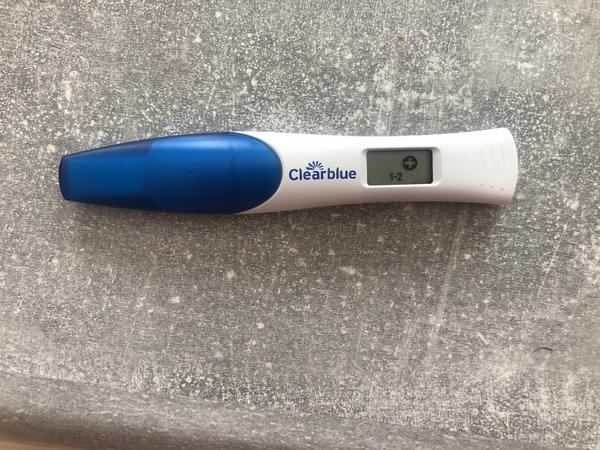

Mne dnes meska 5 dni. Myslite, ze uz by mohol vyjst test pozitivny ak by nahodou?